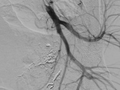

Hình ảnh sau nút mạch quanh động mạch trực tràng của bệnh nhân (Ảnh - BVCC)

90 phút “cân não” cứu sống sản phụ bị tổn thương động mạch trực tràng lần đầu tiên xuất hiện ở VN